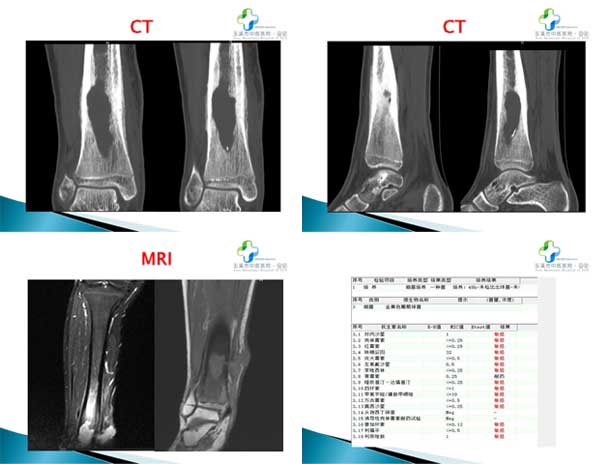

近期玉溪市中醫(yī)醫(yī)院小兒骨科收治了一名慢性骨髓炎的患兒。王某,男,14歲,2022年6月因打籃球扭傷致右踝關(guān)節(jié)腫痛,于當(dāng)?shù)蒯t(yī)院就診,X片示:未見明顯異常。后于當(dāng)?shù)卦\所行針灸、外敷中藥治療。2023年12月打籃球再次扭傷,于當(dāng)?shù)蒯t(yī)院再次就診,X片示:右脛骨下段骨質(zhì)病變。2024年04月MRI示:考慮良性骨質(zhì)病變。2024年6月SPECT/CT示:多考慮感染性病變(慢性骨髓炎可能);期間因發(fā)熱(38.5℃),到當(dāng)?shù)卦\所予以頭孢呋辛治療,效果不明顯。

因病情無明顯好轉(zhuǎn),為求治療遂至我院小兒骨科就診,門診以“右脛骨下段慢性骨髓炎”收住入院。入院癥見:右小腿遠(yuǎn)端內(nèi)側(cè)紅腫、疼痛,可見一直徑約2cm圓形包塊,質(zhì)軟,有波動感,皮溫稍高,右踝關(guān)節(jié)活動受限,無發(fā)熱等癥狀。入院后積極完善相關(guān)檢查,經(jīng)過科室研究,予病灶徹底清創(chuàng),骨水泥鏈珠置入,后期人工植骨,術(shù)后恢復(fù)良好。